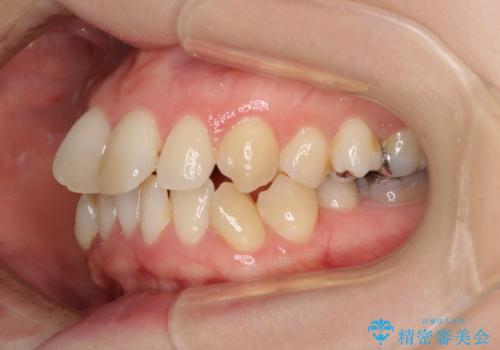

- 奥歯のむし歯を気にして来院された患者様です。

当初は右下の虫歯治療のみを希望されていましたが、虫歯治療に際して部分矯正が必要であったため、治療方法について説明をすると、全体的に歯列不正が気になっているとのことで、全顎矯正を検討することとなりました。

口元の突出感とデコボコがあり、上下左右の小臼歯4本を抜歯して矯正治療を行う方針としました。(右上は欠損のため計3本抜歯)

むし歯となっている歯は状態が悪く、将来的に抜歯となる可能性が高かったため、定石で抜歯させる小臼歯の代わりにむし歯となっている大臼歯を抜歯し、ワイヤー装置にて矯正治療を行うこととしました。